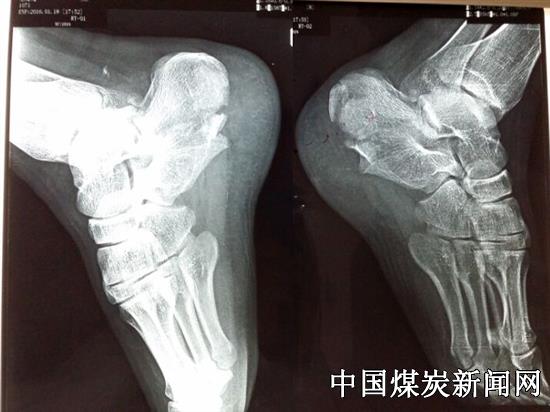

人的足骨有26块,包括跗骨、跖骨和趾骨。跟骨又名脚后跟骨,位于足后下,为七块跗骨中最大的一块,跟骨形态不规则,有六面和四个关节面,还有4沟和5突。跟骨骨折在临床上较为常见,由于其本身的结构复杂,手术中剥离范围大等原因,术后常使钢板外露,切口常感染、坏死,疗效难让患者满意,还易引发医疗纠纷。冀中能源峰峰集团总医院南院区骨六科党员“创客”郭家全多年来迎难而上、不断探索,巧用三件普通小器械和创新的术式治

疗跟骨骨折,成功解决了跟骨骨折难题,并在全院推广,使总医院骨科早已熟练开展跟骨骨折治疗。

以创新理念求解难题。在从解剖上研究了该处切口周围皮肤血管分布情况、分析了出现问题的原因后,郭家全在切口设计中一方面要将跟骨外侧结构保留完整,显露清楚;另一方面要规避损伤血管和神经,尽可能避免血管损伤;切开皮肤时利用克氏针牵开显露,减少对切口皮肤损伤。根据骨折分型,他设计出不同的骨折复位手法及技巧,复位后关节面时,用手外科骨膜剥离器可以一次将跟骨解剖复位,复位完成后跟骨几乎没有骨质缺损,避免了植骨;手术透视也只需一次,减少了放射辐射。他还有独特的切口缝合方法,术后的手术切口几乎无红肿及渗出。独到、创新、科学的设计使手术消除了切口不愈合等问题,经过不断改进和完善手术方案,现在不需助手牵拉,一人即能完成此类手术,大大提高了医疗效率。